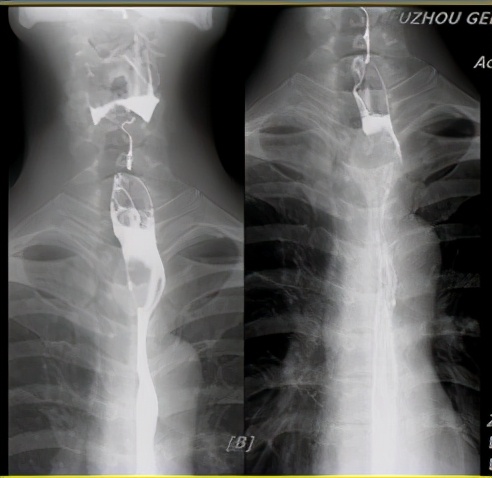

治疗前食管钡餐